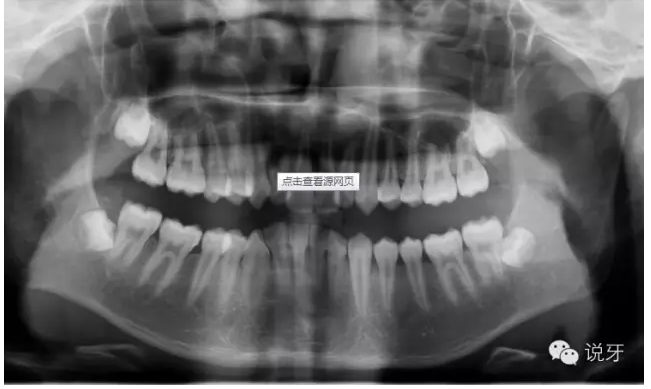

2、拍片

拍X光牙齒及頭部骨頭照片。目的是為了看清牙齒及骨骼發(fā)展方向,以利于之后制定準(zhǔn)確的矯正方法。

QQ圖片20150730111049.png